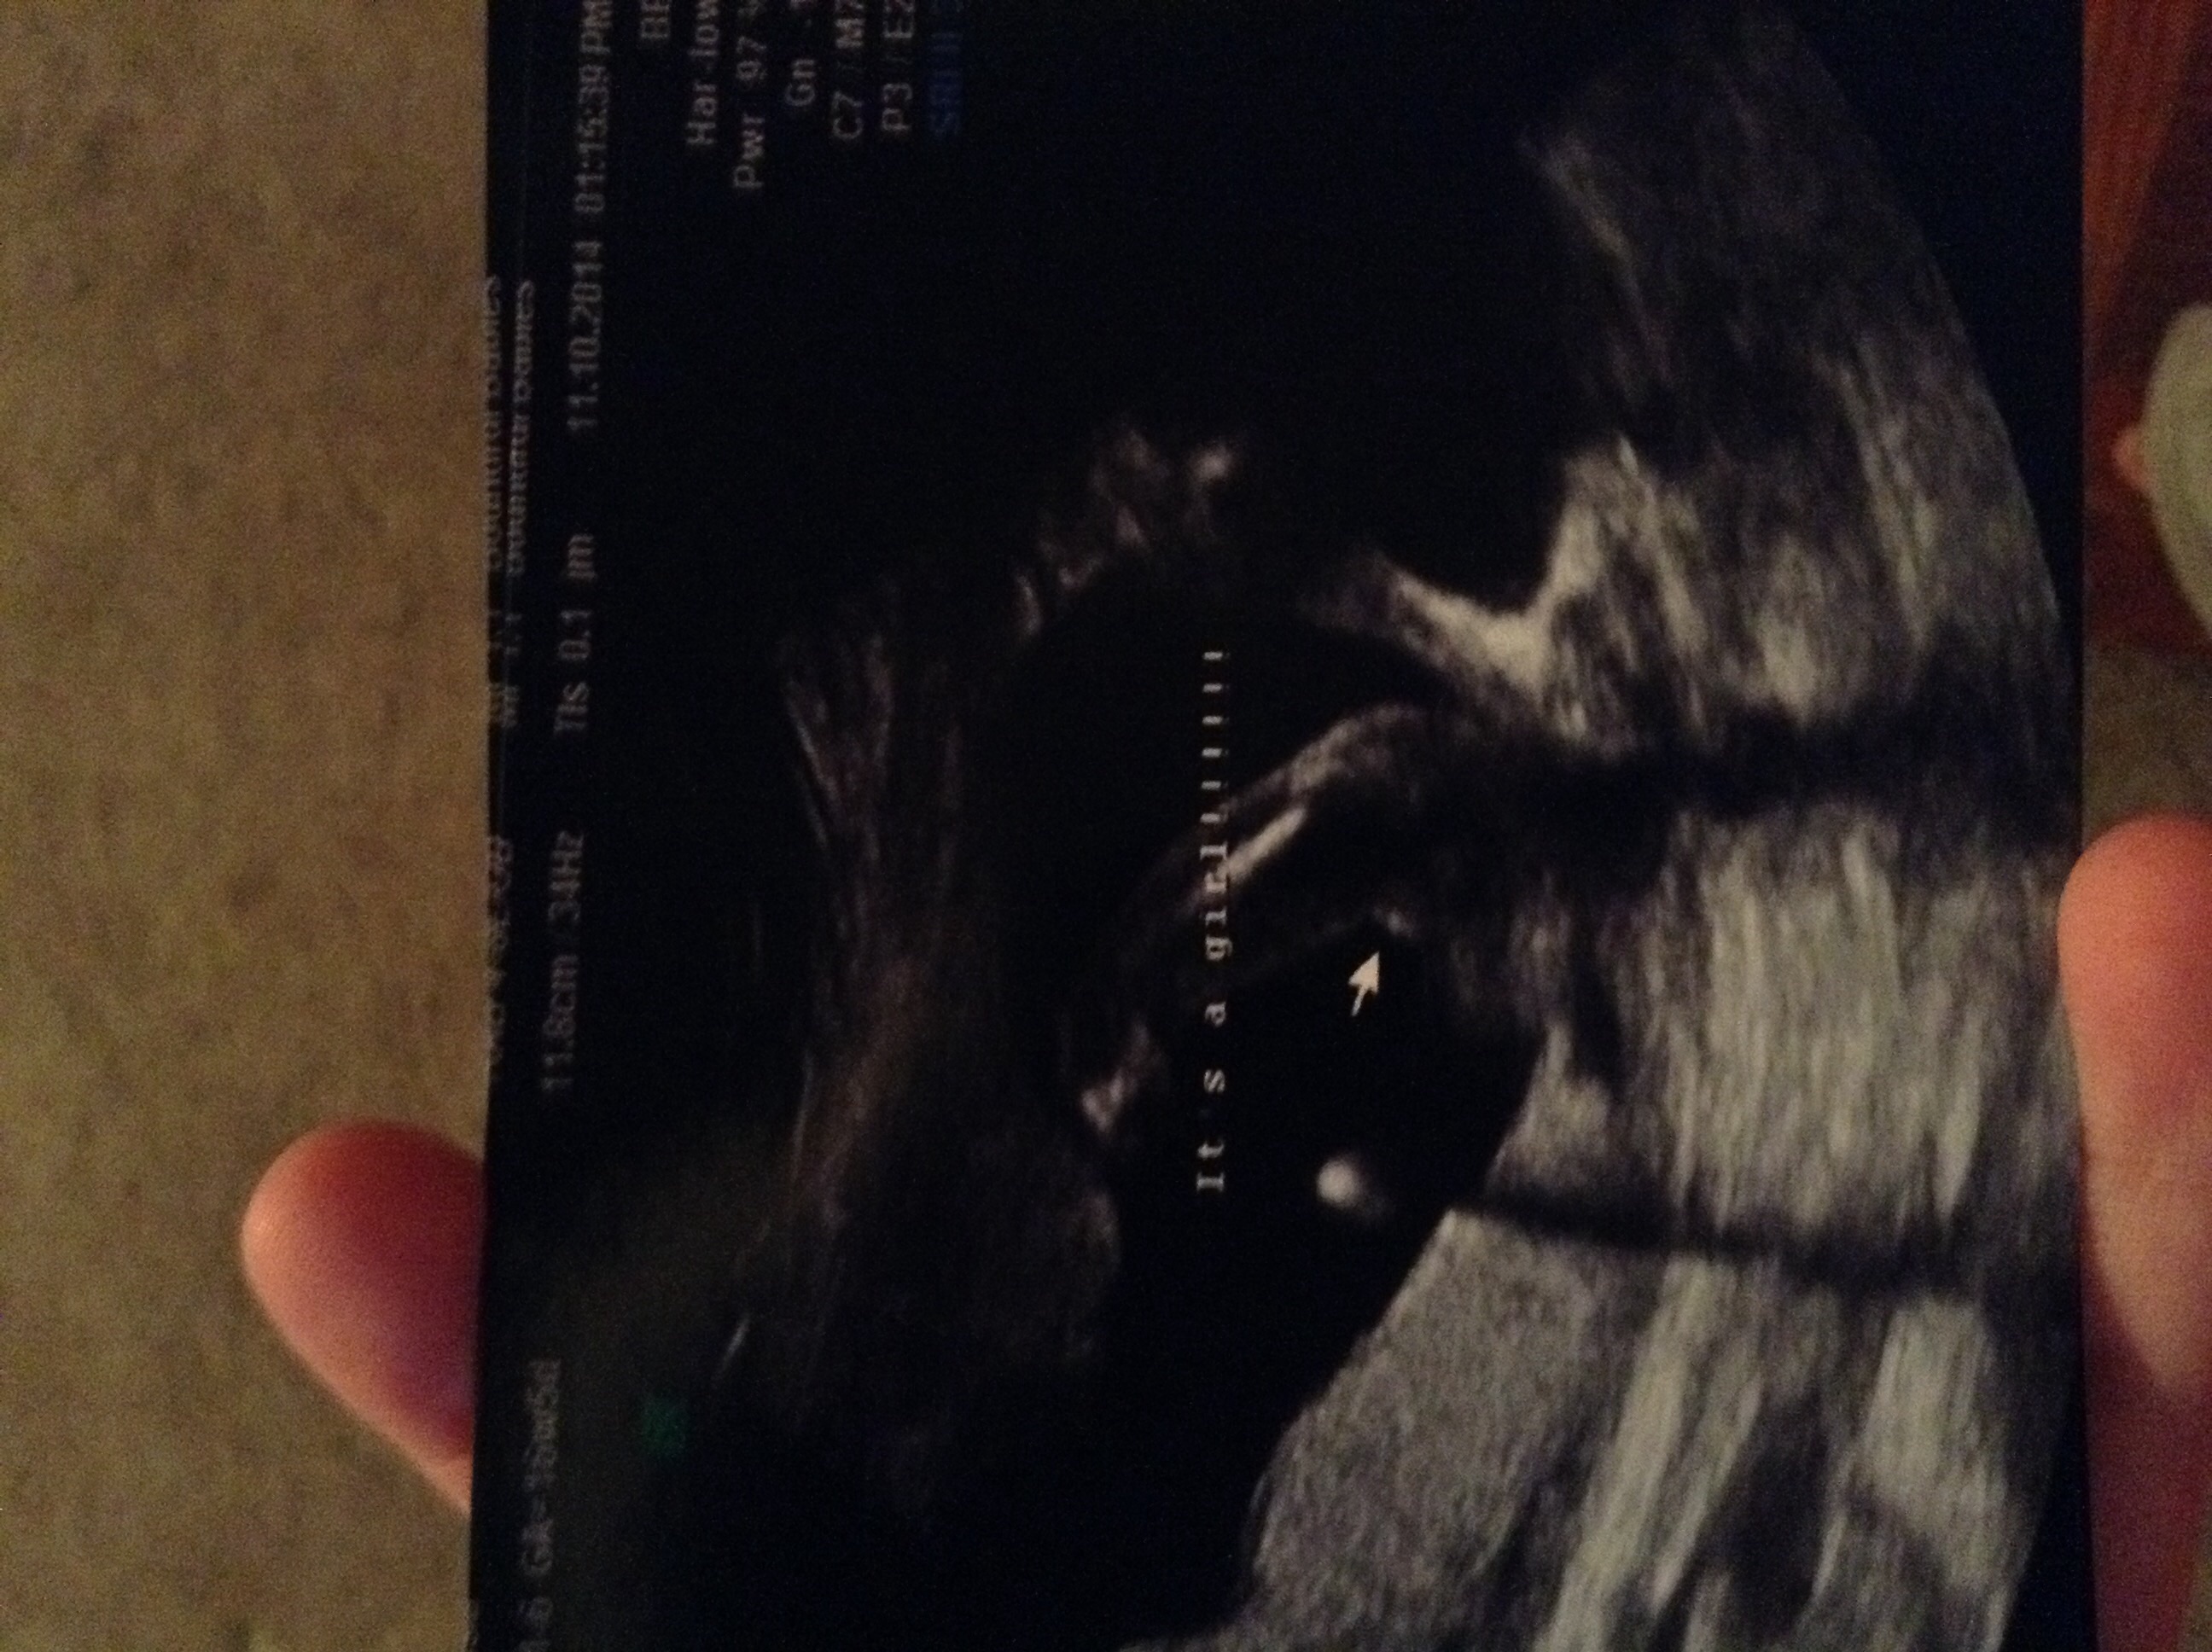

12 weeks 3 days. Tech told me girl and I'm over the moon but I think the potty shot looks like a boy... Opinions please!!!!

I'd really, really, really take that with a grain of salt. 12+3 is really too early to guess on anything but a nub. And even nubs at that stage are not really as accurate as you are looking for. I'd try to keep in mind that it still might be a boy. Not because I think the tech is necessarily wrong, but I think it's a tad irresponsible of a tech (even a trained one) to guess so definitively that early.

Hmmm. Honestly from these I'd say boy. It's still early though.

i agree with Abi, i lean blue as well, but even with the best shot nothing is 100%. It was really irresponsible for anyone to tell you that it was a girl with anything more than a guess

I think the skull is boyish and to me the nub seems on the rise. Again, it's early.

This is what I see...based on the skull theory, it's a boy because the forehead is flat and the back of the head is very round (girls have round foreheads and flatter backs of skulls based on the theory). Also, the nub seems on the rise, as shown. Take this with a grain of salt as baby is not flat on his-her back and the full spine is not seen. Don't hold me to it or be sad...these pics are early and not the best for gender.

In the pic where she captions its a girl!... i thought the line thing she was pointing to was a boys little dingle?

Nub looks very girly to me.

Yes! Just got home and tech said 99% girl!!!!! :cheer: